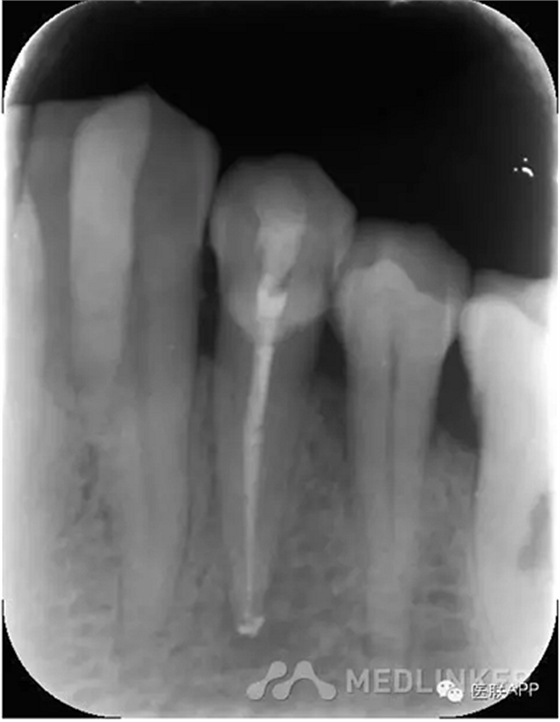

復診:去暫封,超聲蕩洗,干燥,試尖可,糊劑+熱牙膠根充,玻璃離子暫封,3月后復診,囑勿用患牙咬硬物。